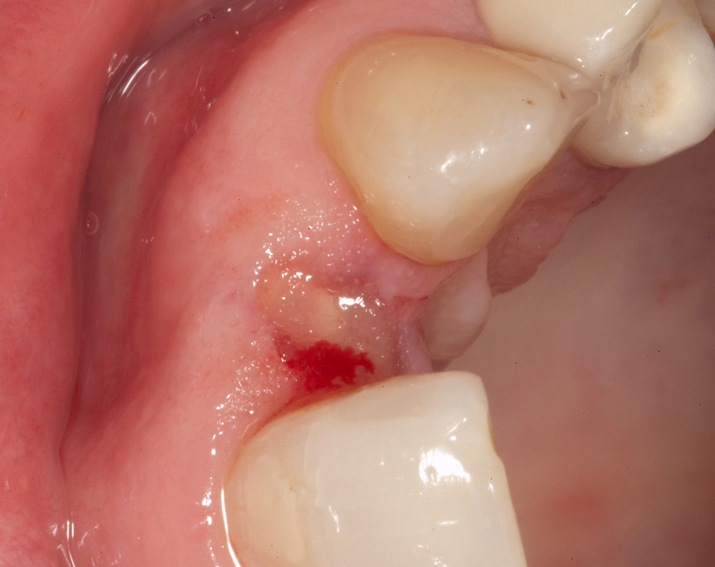

Zeramex T Implantat für Zahn 22

Ein Projekt aus dem Jahr 2013

Im vorliegenden Patientenfall musste der Zahn 22 nach erfolgloser Endodontie entfernt werden. Die Nachbarzähne waren kariesfrei, es wurde eine Marylandbrücke (eine Brücke mit zwei Flügelchen, die palatinal an den Nachbarzähnen verklebt werden) oder ein Implantat besprochen. Die Patientin hat sich für ein Vollkeramikimplantat entschieden. In der Diashow wird der operative Eingriff bis zur fertigen Krone gezeigt. Die Einheilzeit betrug drei Monate.